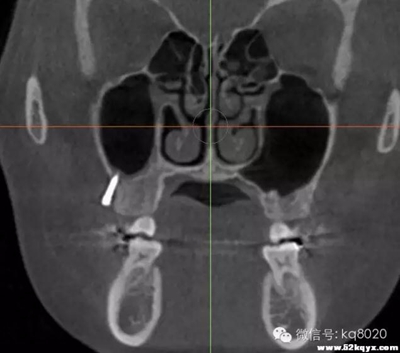

顴牙槽嵴(成人多在67之間,未成年多在56之間或6上方,根據(jù)CT確定)

危險因素:此處植入容易穿破上頜竇底,植入角度需注意;骨質(zhì)較為堅硬,支抗釘易折斷

植入位置和角度:在不滑脫的基礎上越平行于骨面越安全。要根據(jù)顴牙槽嵴的斜度決定植入角度,為避免滑脫,

可先垂直于骨面植入,在調(diào)整方向斜向上,一般植入角度向牙合面旋轉60°-70°